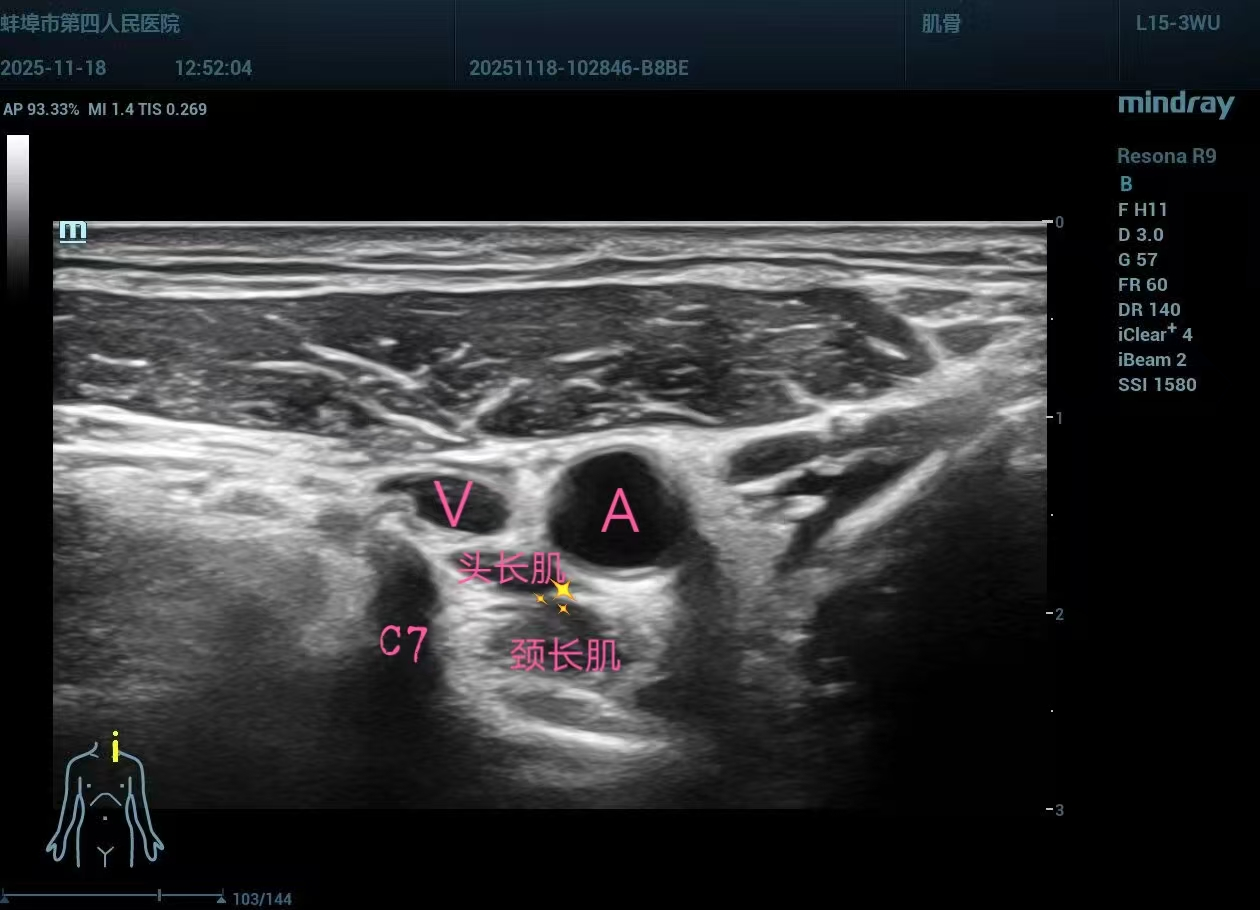

近日,蚌埠市第四人民医院(市康复医院)肌骨超声疼痛治疗团队,在徐晖书记的带领和指导下,成功完成了首例超声引导下星状神经节阻滞技术,此项技术不仅填补了医院在该领域的空白,而且标志着我院在疼痛治疗技术上迈进了新台阶。

超声引导:实时可视化操作,有效避免损伤血管和神经,提升安全性。